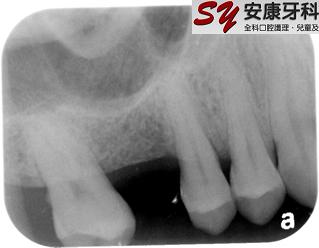

Sinus Lift: (Nov 2008)

There is usually limited bone height for upper back implant due to the presence of maxillary sinus.

Sinus Lift procedure was performed in this case by grafting extra bone into the maxillary sinus at the same time when placing the implant.